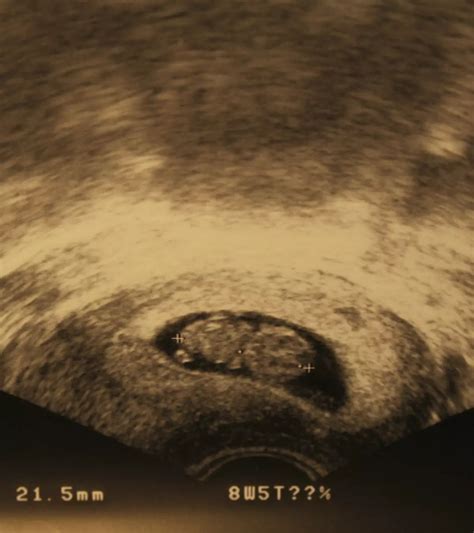

At 9 weeks, the fetus is still very small, but several key features can be visualized:

• Gestational Sac: This is the fluid-filled structure that contains the embryo.

• Yolk Sac: This structure provides early nutrition to the embryo.

• Embryo: The embryo itself, which is about the size of a grape, can be seen with a distinct head and body.

• Fetal Heartbeat: The heartbeat is usually visible and audible, providing reassurance of the fetus’s health.

• Amniotic Fluid: The fluid surrounding the embryo, which protects and cushions the developing fetus.

• Crown-Rump Length (CRL): This is the measurement from the top of the head to the bottom of the buttocks. At 9 weeks, the CRL is typically around 21-27 mm.